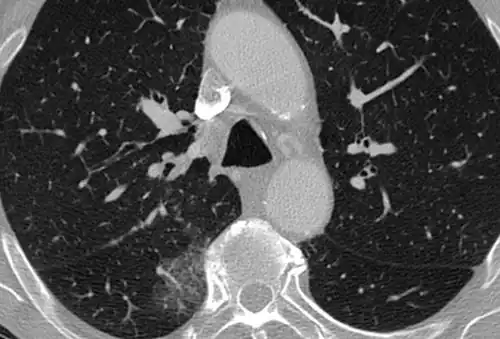

CT image in patient with COVID-19 showing bilateral ground-glass opacities at the periphery of both lungs.

Ground-glass opacity is among the most common imaging findings in patients with confirmed COVID-19.[16][17] One systematic review found that among patients with COVID-19 and abnormal lung findings on CT, greater than 80% had GGOs, with greater than 50% having mixed GGOs and consolidation.[16] GGOs with mixed consolidation has most often been found in elderly populations.[18] Several studies have described a pattern among initial, intermediate, and hospital discharge imaging findings in the disease course of COVID-19. Most commonly, initial CT imaging reveals bilateral GGOs at the periphery of the lungs. During initial stages, this is most often found in the lower lobes, although involvement of the upper lobes and right middle lobe has also been reported early in the disease course.[16][18] This is in contrast to the two similar coronaviruses, SARS and MERS, which more commonly involve only one lung on initial imaging.[19][20] As the COVID-19 infection progresses, GGOs typically become more diffuse and often progress to consolidation.[11][18] This is sometimes accompanied by the development of a crazy paving pattern and interlobular septal thickening.[18] In many cases the most severe pulmonary CT abnormalities occurred within 2 weeks after symptoms began.[17] At this point, many individuals begin showing resolution of consolidation and GGOs as symptoms improve. However, some patients have worsening symptoms and imaging findings, with further increase in septal thickening, GGOs, and consolidation. These patients may develop lung "white-out" with progression to acute respiratory distress syndrome (ARDS) requiring treatment escalation.[17][21]

Preliminary reports have shown many patients have residual GGOs at time of discharge from the hospital. Due to the novelty of COVID-19, large studies investigating the long-term pulmonary CT changes have yet to be completed. However, long-term pulmonary changes have been seen in patients after recovery from SARS and MERS, suggesting the possibility of similar long-term complications in patients who have recovered from acute COVID-19 infection.[22]